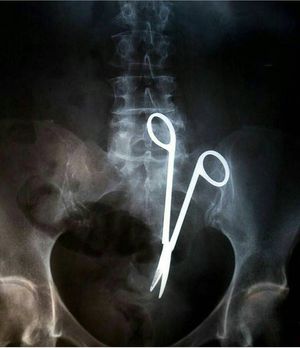

Surgical scissors left in the abdomen

"Hmm, now where did I leave my scissors again?"An x-ray showing surgical scissors left in the abdomen. A pretty big thing to leave behind don't you think?